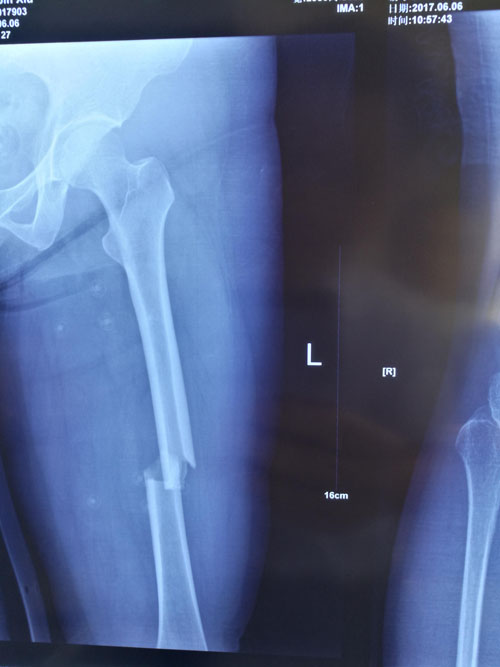

典型病例:閉合復位髓內釘治療股骨骨折,創(chuàng)傷小、出血少,骨折愈合快。